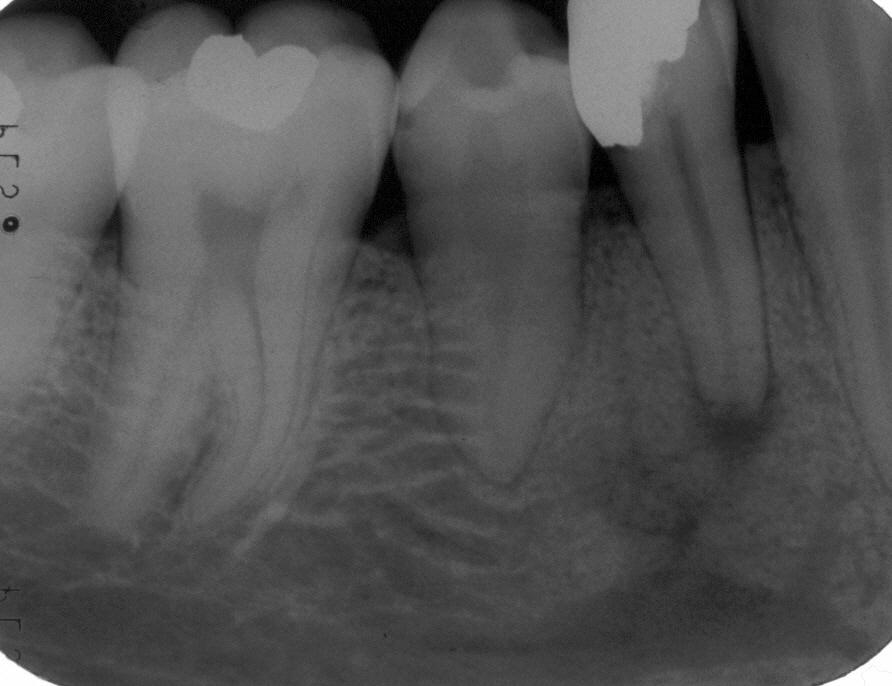

Röntgenologischer Ausgangsbefund im März 1996 bei Zahn 13 mit Silberstiftwurzelfüllung und chronisch apikaler Parodontitis; Zustand vor umfangreicher ZE-Neuversorgung. Erste Therapie der Wahl ist in diesem Fall immer die orthograde Revision

Pat. Initialen: N.D.; Geschl.: Weiblich; Alter: 28